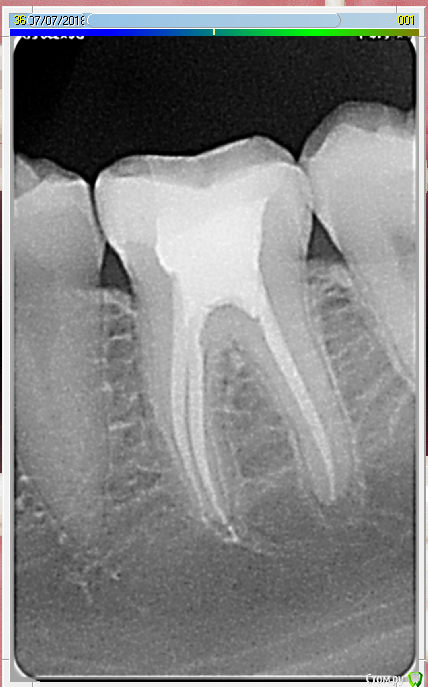

jagaa Опубликовано 10 июля, 2018 Поделиться Опубликовано 10 июля, 2018 (изменено) Прошу прощения, я не понимаю как прицепить снимок в личных сообщениях.Снимок 36го зуба спустя 2 меся после лечения пульпита. Болит даже от воды(( Сказали что нужно все заново делать и давать отток инфекции.. все так страшно?Если у меня есть гарантия на лечение зуба 1 год, его вылечат бесплатно или же по-новой платить? Заранее спасибо Администратор, удалите пож-та предыдущую мою тему Изменено 10 июля, 2018 пользователем jagaa Ссылка на комментарий

St. Опубликовано 10 августа, 2018 Поделиться Опубликовано 10 августа, 2018 вот панорамный снимок. Радует, что нет зубов мудрости хоть)))) Да, и с остальными зубами все достаточно хорошо. В 6 возможно спрятан пропущенный канал или кусочек нерва где-то остался, т.к. по рентгену 3 канала закрыты на всю длину. Лучше сделать КТ чтоб точно знать сколько каналов.И да, скорее всего придется перебирать каналы Ссылка на комментарий